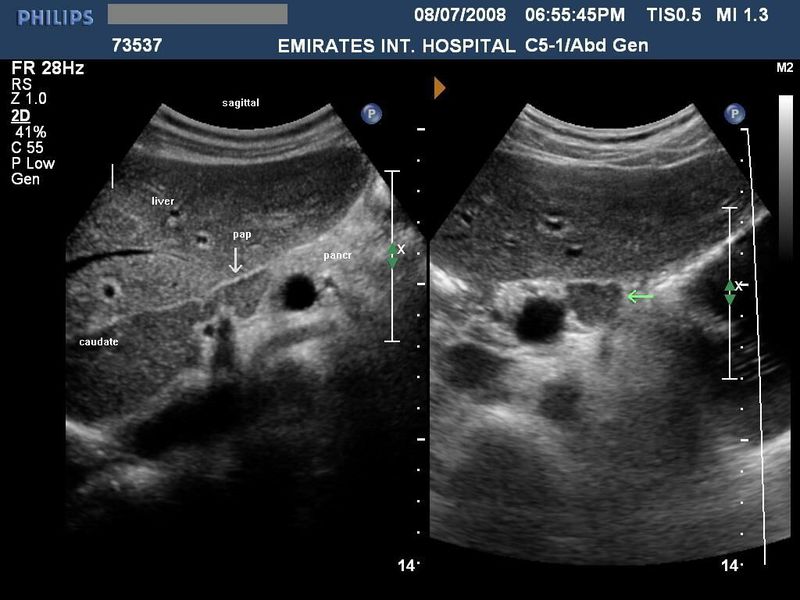

The papillary process of the caudate lobe of liver

1                                   2                                     3                                              4

This patient presented with abdominal discomfort and underwent sonography of the abdomen. Ultrasound images show a rounded mass in the region of the pancreatic head and isthmus. It shows the same echogenicity as the liver(see 1 and 2). This suggested the possibility of a pancreatic mass, possibly malignant. However, images 3 and 4, reveal a different diagnosis- the possible "mass" appears to be an extension of the caudate lobe of the liver. These ultrasound images are diagnostic of "papillary process of the caudate lobe of liver."This normal variant may thus mimic pancreatic or preaortic lymph node masses.

Images courtesy of Dr. Ravi Kadasne, UAE.